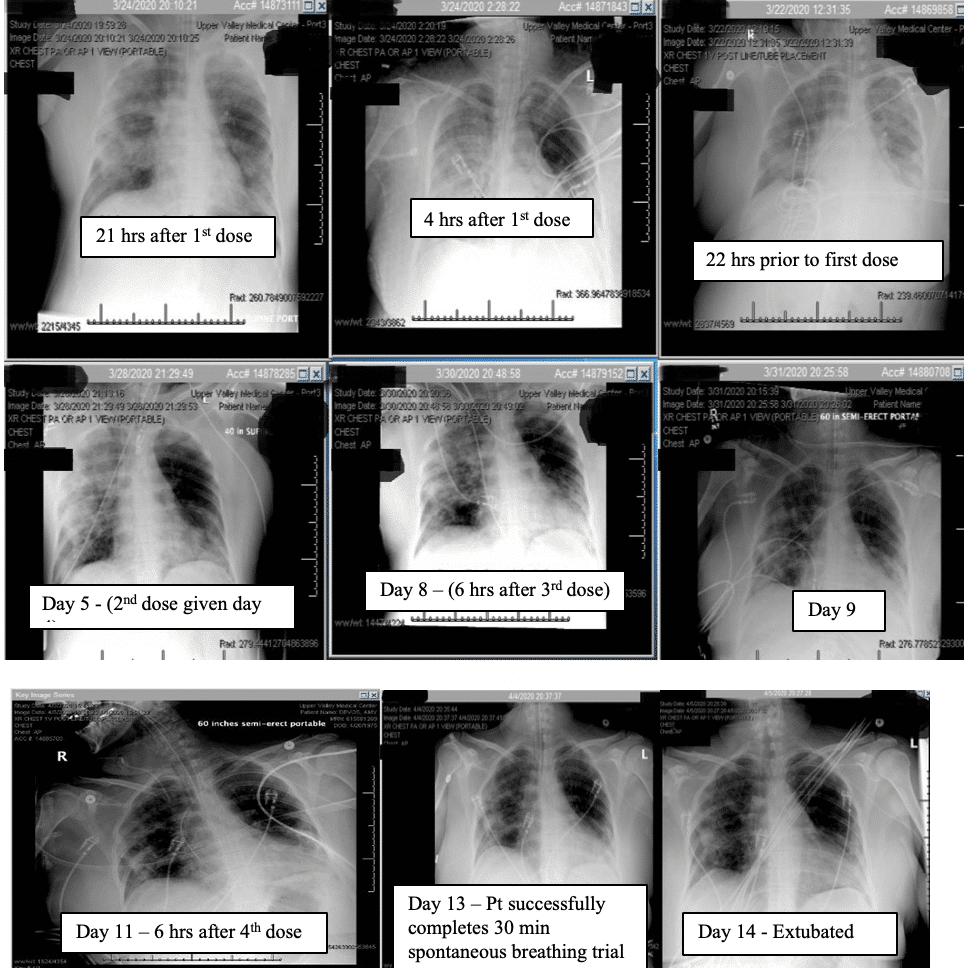

Within 4 hours after the first dose of eculizumab her chest x ray improved, and her Murray score improved from 13 to 10. She had a daily improvement in Murray score except on March 27th 2020 when her endotracheal tube moved out of place while she was prone and had to be readjusted in which case her Murray score rose slightly but still remained lower than her pre-trial baseline. Another 900mg IV eculizumab dose was given 4 days after the first dose and, again, her chest x-ray improved. Her hydroxychloroquine was stopped on March 28th 2020 due to possible contribution to a normocytic anemia. Norepinephrine was discontinued on March 29th 2020 as her blood pressor stabilized. The patient was able to be adequately oxygenated in the supine position and her rotabed was discontinued on March 31st 2020. On April 2nd 2020 her third dose of eculizumab 900mg IV was given and her Murray score improved from 8/16 on April 1st 2020 to 6/16 recorded 7 hours after the third dose of eculizumab was given on April 2nd 2020. On April 3rd 2020 the medical critical care team started to wean the patient’s sedation (propofol, fentanyl, and midazolam). The patient passed a 30 spontaneous breathing trial and followed appendicular commands on April 4th 2020. Mechanical ventilation was continued to allow the sedation to fully wear off in preparation for extubation. The patient’s Murray score had decreased to 3/16, she was able to oxygenate in the supine position, remained afebrile, and did not require presser medications. She was successfully extubated on April 5th 2020. She was neurologically intact and even “face-timed” on the phone with family a few hours subsequent to extubation.

It is also critical to point out that the patient was intubated and almost died while on hydroxychloroquine chronically and did not clinically improve with the concomitant administration of azithromycin. It was not until eculizumab was delivered that the patient began to improve (see chest x-ray for hours after the first dose). The patient also continued to improve despite hydroxychloroquine being stopped by the infectious disease consultant due to a concern for anemia.